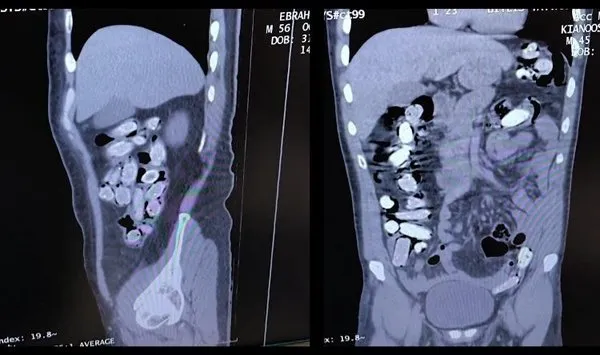

Bitlis Tatvan Devlet Hastanesine götürülen şüphelilerin röntgen ve tomografilerinde, mide ve bağırsaklarında çok sayıda yabancı cisim olduğu belirlendi.

Şüphelilerin yuttuğu 136 kapsüldeki 1 kilo 48 gram sentetik uyuşturucu, tıbbi müdahaleyle mide ve bağırsaklardan çıkarıldı.